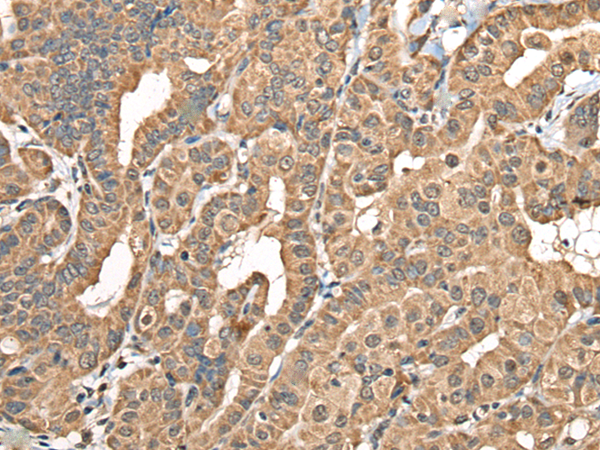

NADK2 |

Immunogen: |

Fusion protein of human NADK2 |